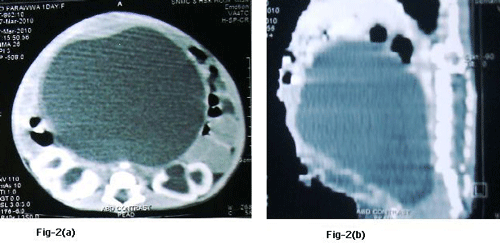

A large abdominal mass displacing the bowel to upper abdomen was seen on plain abdominal radiograph. Ultrasound and CT scan findings (Fig. 2a and 2b) were consistent with the huge HMC compressing rectum and bladder. There was associated bilateral hydroureteronephrosis on CT scan. There was no communication between the bladder and vagina on genitogram (Fig. 3), which was done postoperatively. Neonatal cystoscope was not available at our centre to establish this finding. Echocardiography showed ASD. A cutaneous vaginostomy was created and Foleys catheter left in situ for 10 days. The neonate had an uneventful recovery and from postoperative day 1 baby started passing stools. Child is now thriving well and is 1 year old. She has been planned for definitive surgery.

Figure 2 (a, b): CT images showing severe hydrometrocolpos.